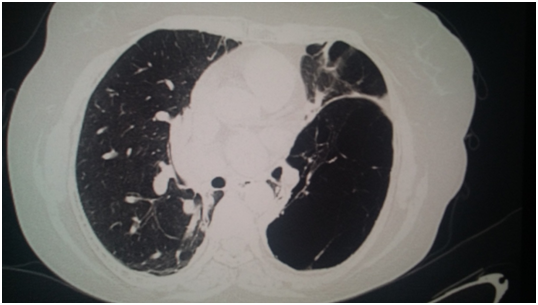

Female of 59 years old, exposed to biomass smoke (index=100 hrs/year), followed as Chronic Obstructive Lung Disease during 9 years; her main symptom has been dyspnea, vital signs HR 86 per min, RR 20 per min, 110/78 mmHg, body temperature 36.6°C, very severe obstruction in spirometry, low Diffusion Capacity, increased Residual Volume, Pulmonary Arterial hypertension by echocardiography (47 mmHg) and arterial gases pH 7.38, PaCO2= 47 mmHg, PaO2 66 mmHg, HCO3 =21.6 and O2 saturation 92.5% with oxygen supply. Radiographic studies Figure 1 showed, bullous emphysema at left lung in conventional chest radiography; and, neurofibromatosis lesions in both hands (Figure 2) and feet (Figure 3) and Computed tomography revealing bilateral emphysema and bullae (Figure 4).

Figure 3 Bullous emphysema 1.